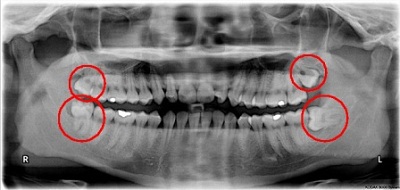

Các loại hình nhân viên y tế mắc hội chứng “Burnout” (tại Mỹ, năm 2018)

Điều đáng lo ngại hơn là hội chứng “Burnout” gần như là hội chứng khá đặc thù dành riêng cho nhân viên y tế không chỉ xảy ra ở các bác sĩ điều trị, mà nó còn ảnh hưởng và tác động lên cả các loại hình nhân viên y tế khác. Khảo sát mới đây vào tháng 4/2018, nhóm nghiên cứu về quản lý y tế thuộc Tạp chí New England Journal of Medicine cho thấy hội chứng “Burnout” còn xảy ra ở người điều dưỡng trực tiếp chăm sóc người bênh (RN), điều dưỡng chuyên khoa (APRN), bác sĩ trưởng khoa lâm sàng, và cả các nhà quản lý bệnh viện. Trong đó, điều dưỡng trực tiếp chăm sóc người bệnh có tỉ lệ mắc hội chứng “Burnout” là cao nhất (78%), kế đến là các điều dưỡng chuyên khoa (64%), các bác sĩ trưởng khoa (56%) và các nhà quản lý bệnh viện (42%).